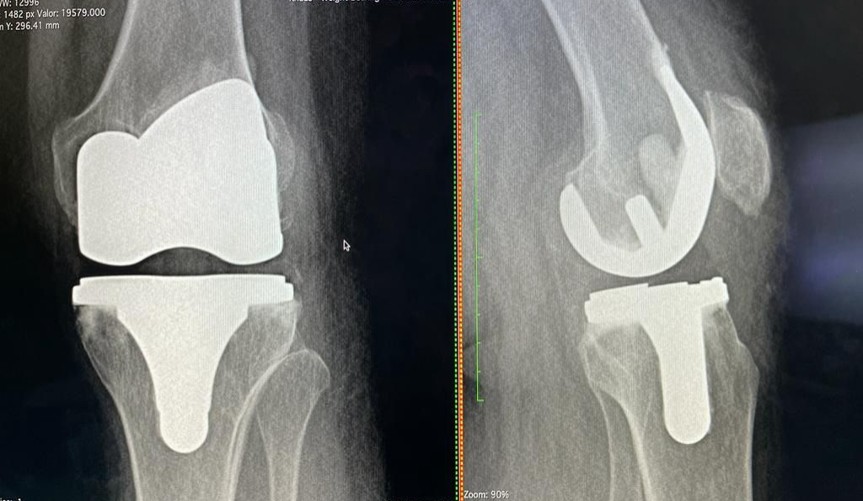

Artrosis de Rodillas (Osteoartritis de Rodilla)

La artrosis de rodillas es una enfermedad degenerativa crónica que afecta el cartílago articular, el tejido que cubre los extremos de los huesos y permite un deslizamiento suave en la articulación. Con el tiempo, este cartílago se desgasta, volviéndose áspero y delgado, lo que lleva a un rozamiento directo entre los huesos.

- Tratamiento Quirúrgico: Cuando el tratamiento conservador no es suficiente y el dolor limita severamente la calidad de vida.

- Artroscopia: Para limpiar la articulación o reparar daños menores.

- Osteotomía: Realineación de los huesos para redistribuir la carga.

- Artroplastia (Reemplazo Articular): En casos avanzados, se puede realizar un reemplazo total o parcial de la rodilla por una prótesis, lo que alivia el dolor y restaura la movilidad.